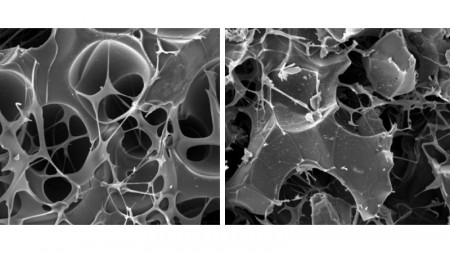

Imagens de microscopia da estrutura dos biomateriais testados na recuperação de fraturas durante o estudo; à direita, matriz de carbono; à esquerda, a mesma matriz associada a nanografite (imagem: Daniela Franco Bueno et al.)